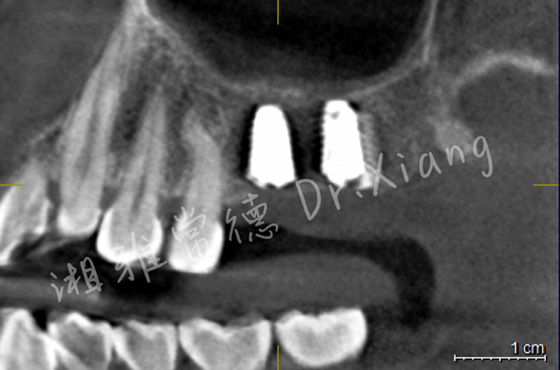

經(jīng)過9個月骨愈合后,患者復(fù)查錐形束CT,骨愈合十分滿意。9月中旬,向峰醫(yī)師種植團隊成功為患者實施了第二步的手術(shù),取出內(nèi)固定裝置的同時為患者成功微創(chuàng)的植入2枚種植體,完成了患者左上頜區(qū)域的軟硬組織的自然恢復(fù)和改建。

接下來,患者即將進入治療的“最終章”。3個月后取模,完成種植牙冠的修復(fù),重建缺失的牙齒。

種植體精準微創(chuàng)植入